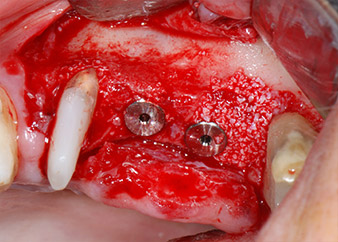

En el siguiente paso, los lechos del implante se prepararon en las posiciones 25 y 26 con instrumentos rotatorios, utilizando un contra-ángulo con un coeficiente de transmisión de 20:1 (WS-75 L, W&H), junto con el nuevo potente motor de implantes Implantmed de W&H (figuras 8 y 19).

A continuación, los implantes (Restore, Keystone Dental, 3,75 mm de diámetro, 8,0 mm de longitud) se colocaron con el motor de implantes (figuras 11 y 12).

Las deficiencias óseas alrededor de los implantes, en el área mesial de la pieza 27 y alrededor de la raíz bucal de la pieza 24, se obturaron con partículas sustitutas de hueso xenógeno (Geistlich Bio-Oss) y se cubrieron con una membrana de colágeno absorbible (Geistlich Bio-Gide) a efectos de realizar un aumento mediante GBR

(figuras 13 y 14).